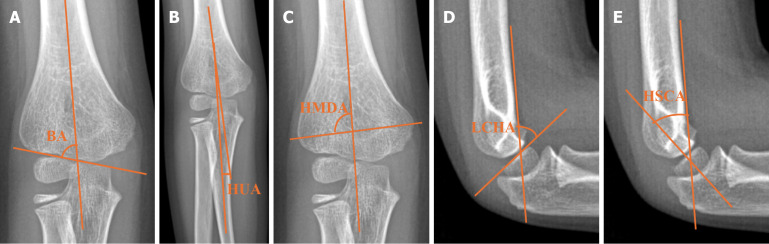

Methods: Radiographs of 78 SCHF patients were analyzed for angular measurements of the contralateral elbow. Two control groups were used: 98 healthy children and 40 patients with DRF. Angular measurements included Baumann angle (BA), humeroulnar angle (HUA), humerus metaphysis-diaphysis angle (HMDA), humerus shaft-condylar angle (HSCA), and lateral capitellohumeral angle. Only BA, HUA, and HMDA were measured in the DRF group. Statistical analysis was performed to compare differences among groups.